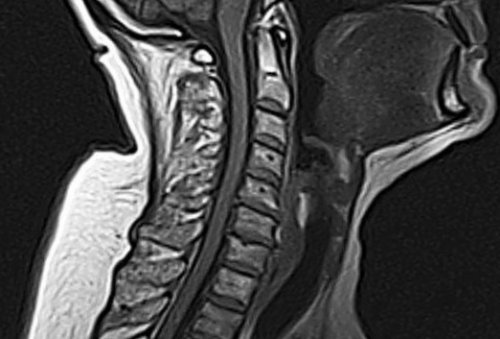

Рентгенография поможет выявить наличие остеофитов, смещение позвоночных сегментов, наличие осложнений. КТ покажет, сдавлены ли нервы, какова на данный момент высота дисков и даст полное представление о состоянии шейного отдела, поможет определить степень развития патологии. МРТ позволит получить максимально точную картину состояния всех структур позвоночного столба в области шеи, а УЗИ даст возможность понять, насколько изменен кровоток в сосудах.

МРТ шейного отдела